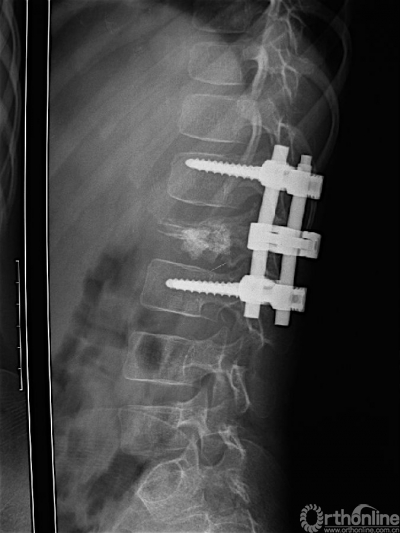

图 2 术后腰椎侧位片,L2椎体病变刮除彻底,植骨充分,内植物位置良好。